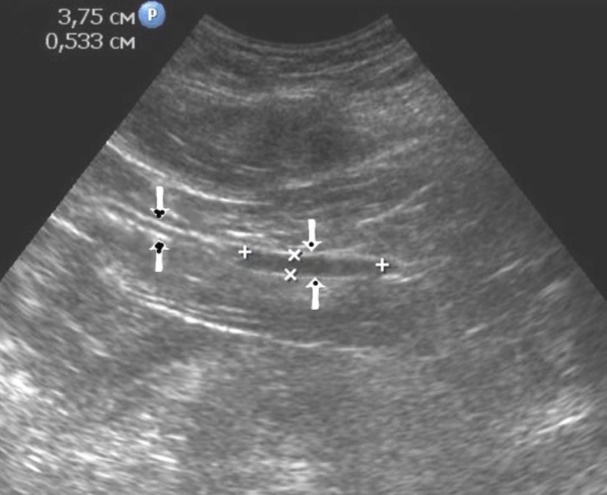

Figure 10.The gastric carcinoma of diffuse infiltrative form. An area with a local thickening up to 1,7 cm, a length of 3,68 cm, is visualized on the anterior wall of the antrum (arrows). The thickening of the normal stomach wall is 0,34 cm.

T2 stage of diffuse carcinoma was recorded in 14 cases – among them 5 cases of ulcerating forms, 5 cases of infiltrative ulcerative forms and 4 cases of diffuse infiltrative forms. Gastroscopy diagnosis was established in all 10 cases of ulcerative and infiltrative ulcerative forms of gastric carcinomas and in 3 cases of diffuse infiltrative forms. Ultrasound diagnosis was established in 13 cases of diffuse carcinoma, except for one case where the location of the ulcerative form was in the fundus of the stomach (Figure 8, Figure 9, Figure 10).